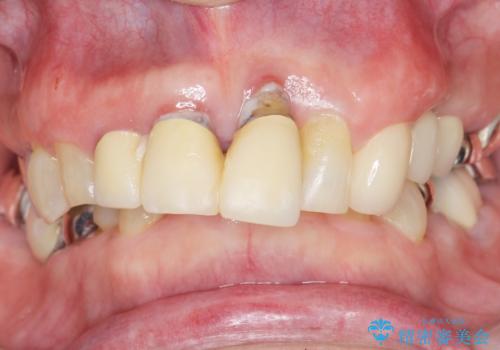

- 左下奥歯の歯ぐきから膿が腫れてきたことを主訴に来院された患者様です。

精査したところ奥歯(左下6)が破折しており、保存不可能と診断されました。

保存不可能な奥歯(左下6)を抜歯し、機能していない親知らず(左下8)の移植を行いました。

移植後、生着を待って根管治療及び補綴修復を行いました。